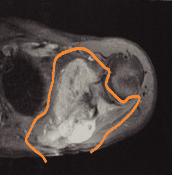

근골격계 병변의 평가에 있어 중요한 방사선 검사로 특히 종양의 진행단계를 결정하는데 필수적인 검사입니다. 조직간의 구분이 명확하고 여러 각도에서 촬영이 용이하여 골종양의 크기나 모양, 주위 조직과의 관계, 혈관이나 신경과의 관계를 잘 알 수 있습니다. 또한 종양의 침범 범위가 될 수 있는 근육, 피하 지방, 관절, 신경 혈관 구조물 등에 대해 정확한 정보를 주므로 사지 구제술(보존술)의 적용 가능성 판정과 절단 시의 절단 범위 결정에 절대적으로 자기공명영상(MRI)검사가 필요합니다. 종양에 대한 항암화학요법 전후에 영상을 비교해 치료 효과 판정에 이용하기도 합니다.

[ 악성 골종양의 자기 공명영상 사진 ]